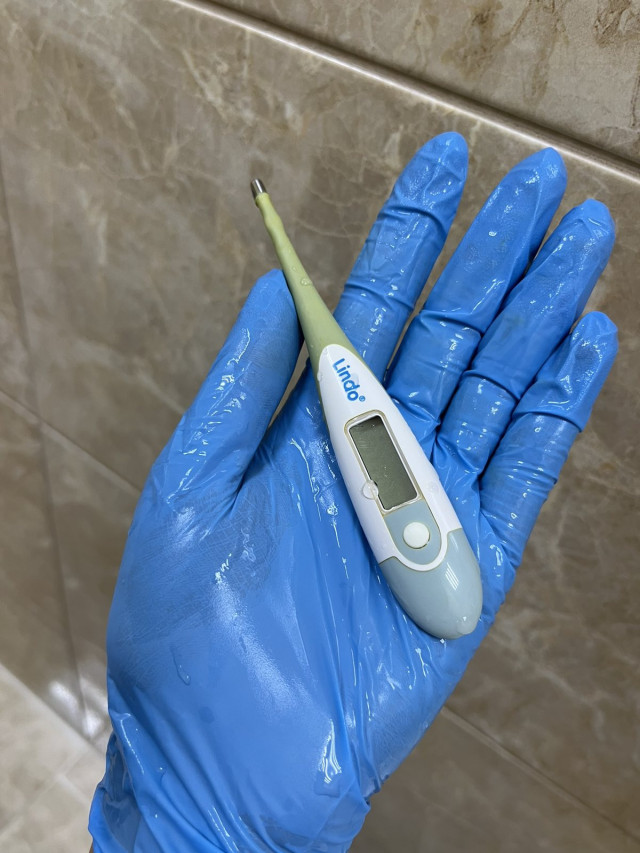

Вчора бригада екстреної медичної допомоги доправила у Волинське обласне медоб'єднання захисту материнства і дитинства із Каменя-Каширського маму із піврічною дитиною. Зі слів мами, у доньки закреп, тож вона намагалася зробити їй клізму за допомогою електронного термометра, змащеного олією, і він повністю опинився в товстому кишківнику дитини.

«На рентгені було чітко видно термометр, також він пальпувався через живіт. Дістати прилад було дуже непросто. Зробили це ендоскопічно, діяти треба було дуже обережно, щоб не травмувати немовляті анус та внутрішні органи. Самостійно градусник вийти не міг, натомість міг перфорувати кишківник або надалі спровокувати кишкову непрохідність», – розповідає хірургиня та ендоскопістка Волинська обласна дитяча клінічна лікарня Юлія Артишук.

«На рентгені було чітко видно термометр, також він пальпувався через живіт. Дістати прилад було дуже непросто. Зробили це ендоскопічно, діяти треба було дуже обережно, щоб не травмувати немовляті анус та внутрішні органи. Самостійно градусник вийти не міг, натомість міг перфорувати кишківник або надалі спровокувати кишкову непрохідність», – розповідає хірургиня та ендоскопістка Волинська обласна дитяча клінічна лікарня Юлія Артишук.